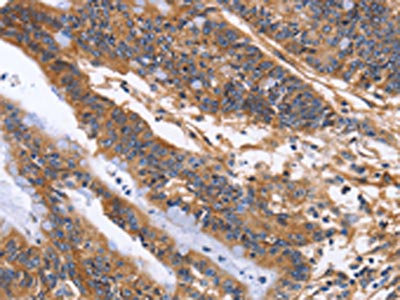

The image on the left is immunohistochemistry of paraffin-embedded Human liver cancer tissue using CSB-PA245433(ITGB1 Antibody) at dilution 1/60, on the right is treated with fusion protein. (Original magnification: ×200)

The image on the left is immunohistochemistry of paraffin-embedded Human colon cancer tissue using CSB-PA245433(ITGB1 Antibody) at dilution 1/60, on the right is treated with fusion protein. (Original magnification: ×200)